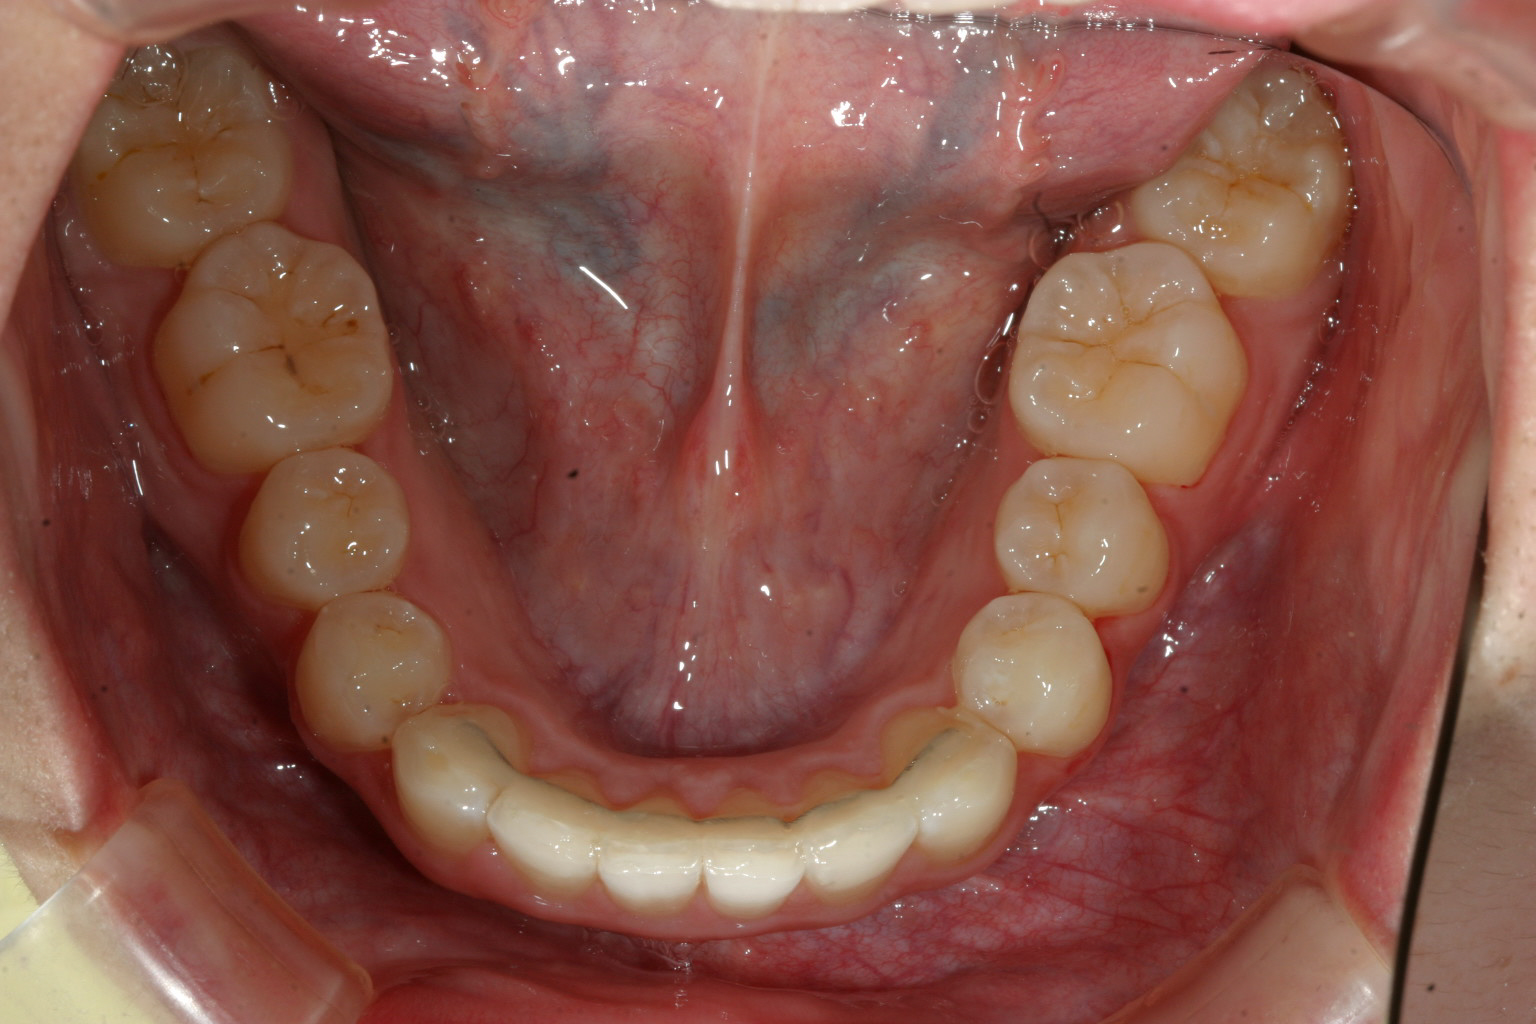

上の歯列がV字型ですから下顎もV字型です。

下顎も綺麗なアーチにしないと噛めませんからね!